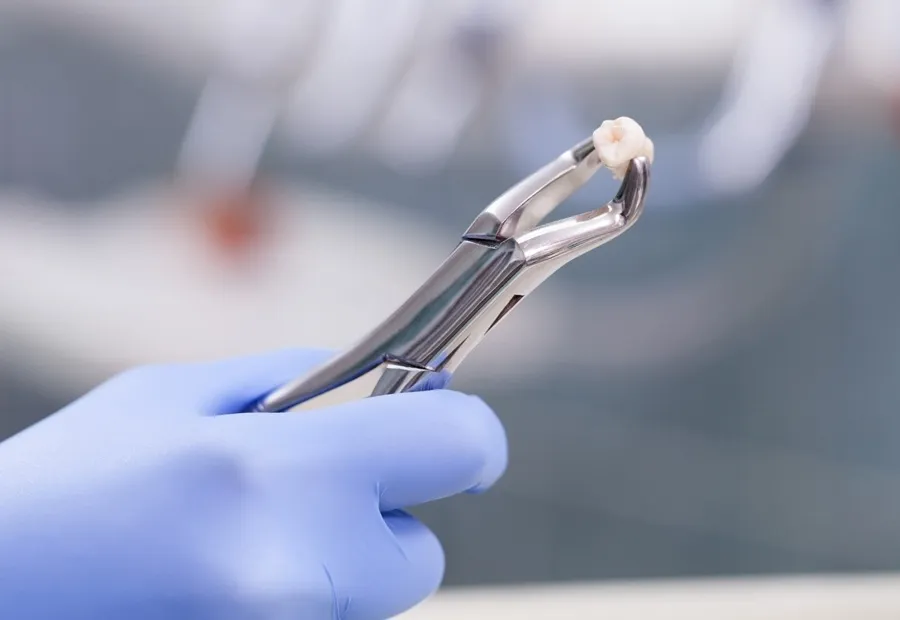

An example of the treatments we have done :

EXAMPLE ORTHODONTIC TREATMENT IN OUR CLINIC

Klinik Trabzon Oral and Dental Health Clinic, located in Trabzon, Turkey, provides comprehensive dental services across all specialties with our experienced physician staff. We specialize in advanced treatments including dental implants, cosmetic dentistry, porcelain veneers, zirconia crowns, orthodontics (including Invisalign), and pediatric dentistry.

With a commitment to excellence and the expertise of our qualified dental team, we are capable of performing all types of advanced oral surgeries and aesthetic transformations in the heart of Turkey.